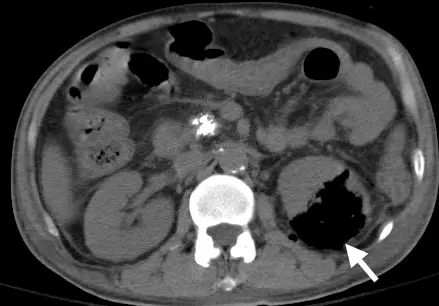

29.電腦斷層檢查如下圖,圖中箭號所示屬於下列何種組織成分?

這是一張腹部無顯影劑電腦斷層 (Non-contrast abdominal CT) 軸切面 (Axial view) 影像(軟組織窗設定):

- 正常結構對比:右側腎臟 (Right kidney) 呈現正常的軟組織密度(灰色);脊椎 (Spine) 與腹主動脈 (Abdominal aorta) 壁上的斑塊呈現極高密度的亮白色,為骨骼與鈣化 (Calcification)。腹壁外圍則可見暗灰色的皮下脂肪 (Subcutaneous fat)。前方腸道內可見極黑的區域,為腸道氣體 (Bowel gas)。

- 病灶特徵:左側腎臟 (Left kidney) 被一個巨大的極低密度(呈現極度黑色,Jet black)區域所占據,即為圖中白色箭號所指處。正常腎臟實質已遭到破壞。

- 密度比對:將箭號所指的極黑區域與皮下脂肪(暗灰)以及腸道氣體(極黑)進行肉眼比對,可以清楚發現該病灶的黑度與腸道氣體完全一致,代表該組織成分為**空氣/氣體